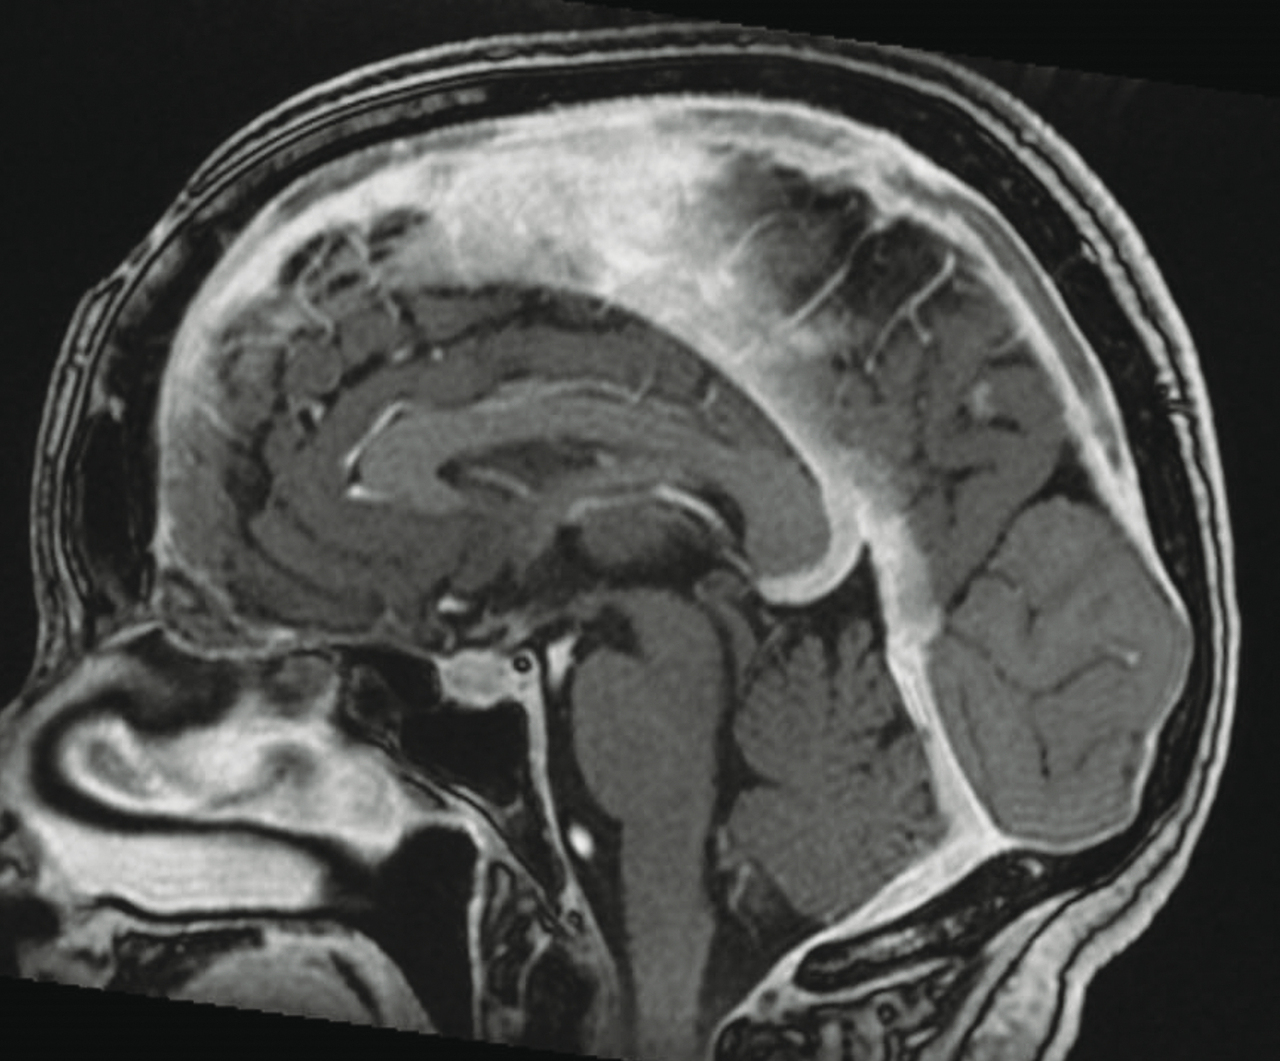

Femme de 72 ans, céphalées , photophobie, absence de fièvre. Quel est votre diagnostic ? Accident vasculaire cérébral Hémorragie méningée Hématome sous-dural Thrombose veineuse cérébrale Vascularite du système nerveux central OK Valider mes réponses